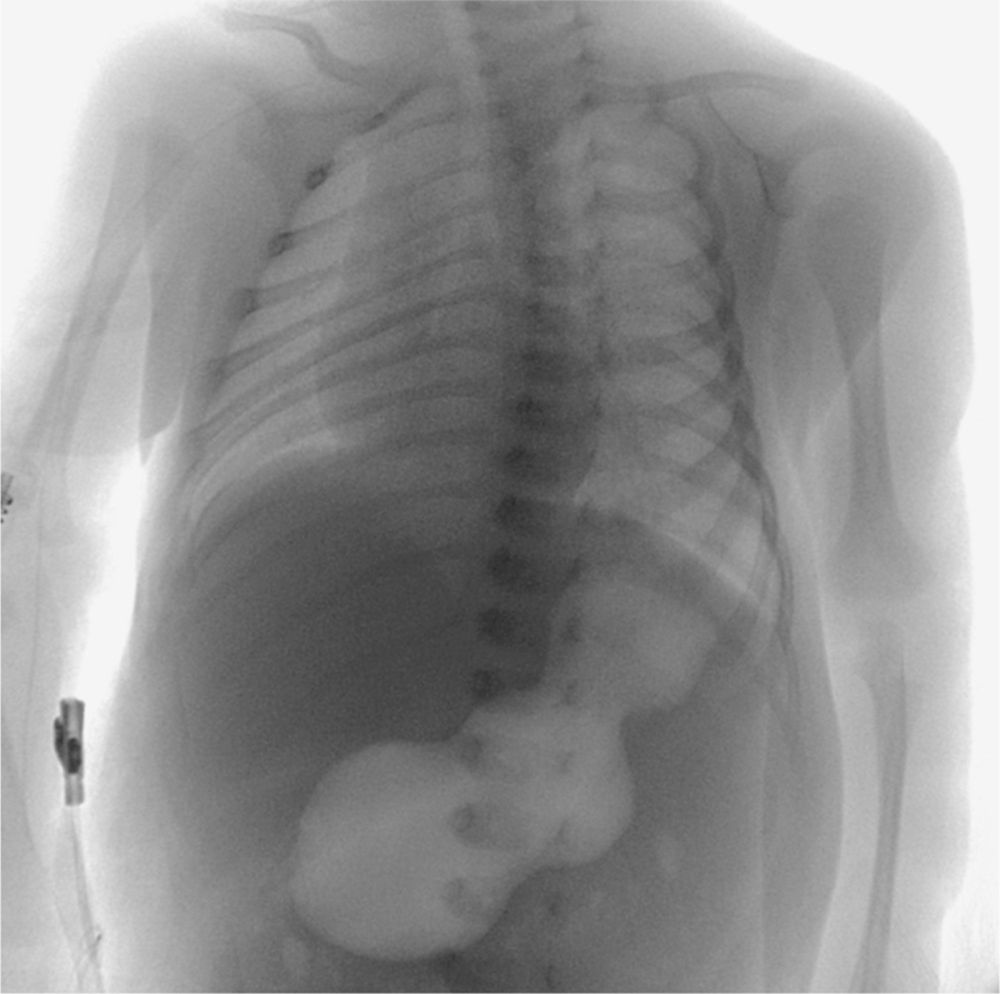

A 23-day-old male infant was brought to the emergency department after 5 days of increasing vomiting. Physical exam revealed mild dehydration and an olive-sized abdominal mass. Upper gastrointestinal radiography showed a distended, air-filled stomach.